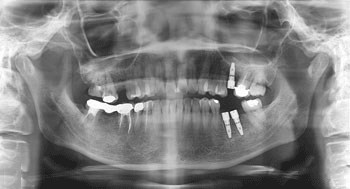

本科室使用国产创英系统、韩国Dentium系统、瑞士ITI系统等一系列先进种植系统,主要开展单牙或多牙缺失的种植修复、全口无牙合的种植固定修复、重度牙周病的种植修复、各类种植覆盖义齿(包括杆卡、球帽、套筒冠、磁性附着体等)、各类植骨技术(包括自体骨转移、人造骨粉等)、上颌窦内外提升、骨挤压技术、骨劈开技术、即刻种植、即刻修复等,同时开展无痛、微创、快捷、美观、舒适的人工种植牙技术,深受广大患者的赞誉,本科室本着服务群众、人们生活水平的宗旨,开展平价、优惠、保质的种植活动,用双手让名副其实的人类第三副牙齿缔造广大患者高品位的人生和灿烂的微笑。